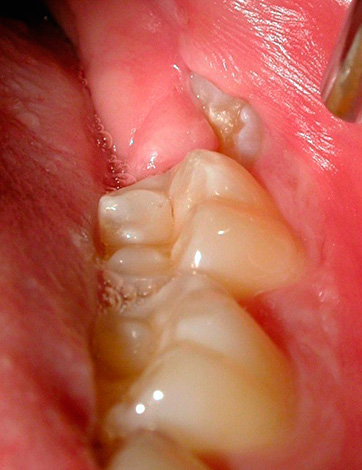

La seguente foto mostra un esempio di un dente del giudizio semi-rinforzato:

Spesso sotto il cappuccio gengivale si accumulano particelle di cibo e batteri, si verifica un processo infiammatorio: la pericoronite. Quando un essudato purulento si forma sotto la gomma, compaiono sintomi che ostacolano la normale vita di una persona: gonfiore nell'area del dente del giudizio, cattive condizioni generali, febbre fino a 38-39 ° C, incapacità di masticare e persino aprire normalmente la bocca, dolore severo, spesso pulsante e irradiante a vari sezioni del viso.